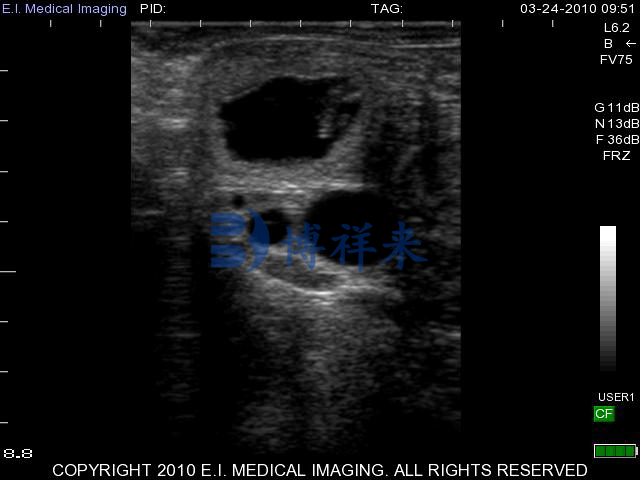

凸阵直肠探头测牛35天超声图

在牛用B超机的妊娠检测或生殖系统检查中,凸阵直肠探头的优势体现在:

视场更大,能够在单次扫描中覆盖更大区域,适合对整个子宫或更深部位的结构进行概览式观察。

较低频率使得声波有更好的深度穿透能力,因此在较深妊娠阶段(如妊娠中后期检查)或需要观察更深层组织时表现更稳定。

对于繁殖疾病等更复杂检查的需求,凸阵探头常被推荐用于扫描更广范围或对深部结构进行成像,以便全面评估结构状态。